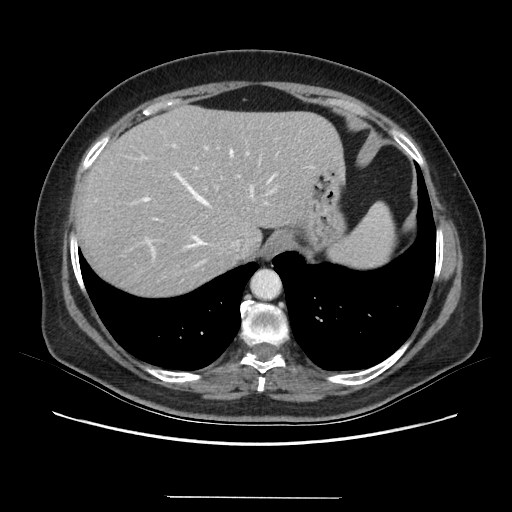

Original VENOUS CT scan

Full window (WL 1023.5, WW 4095 β†’ Low βˆ’1024, High +3071)

Actual HU range: [-1024.0, 884.0]